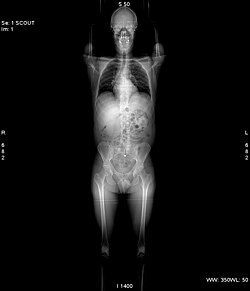

Vor jeder Aufnahme wird grundsätzlich eine Übersichtsaufnahme aufgenommen. Hierbei steht die Röntgenröhre still. Der Patient wird mit Hilfe des verfahrbaren Tisches am Fächerstrahl der Röhre vorbeigefahren. Im Ergebnis erhält man ein Bild, das einer klassischen Röntgenaufnahme sehr ähnlich sieht. Dieses Bild dient jedoch nur der Planung anschließender Aufnahmen.[1]